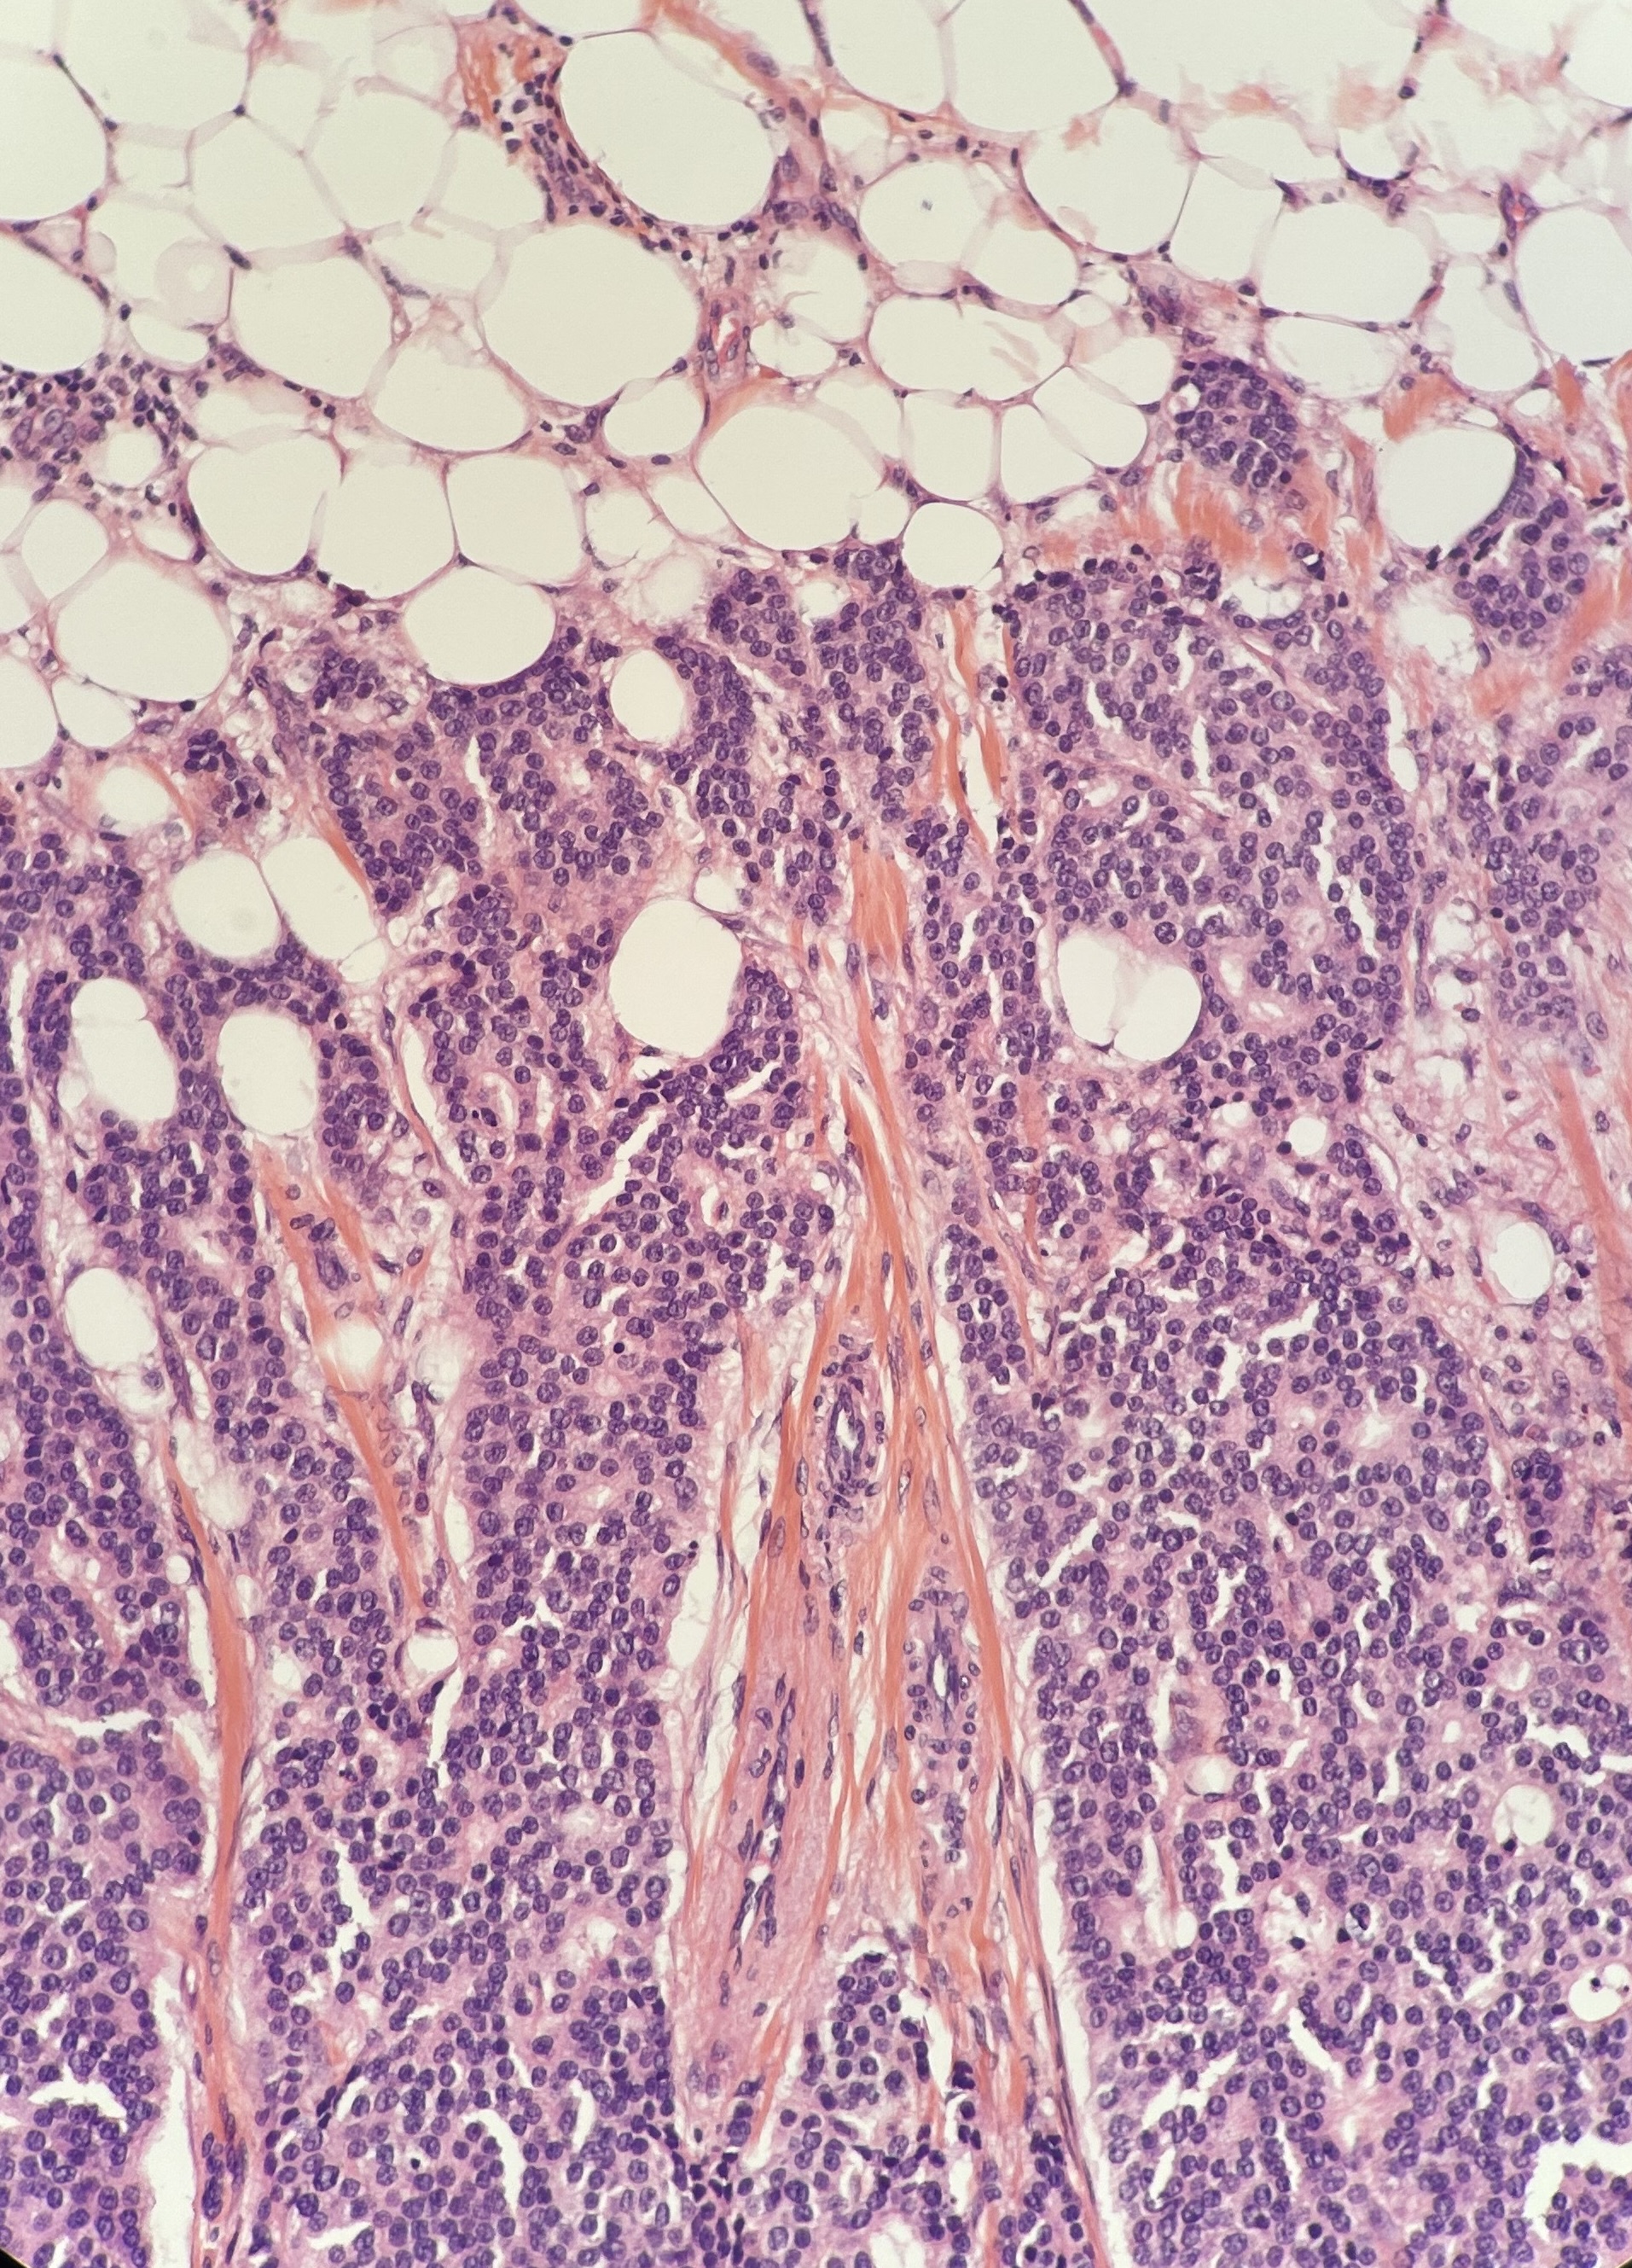

La toute première catégorie de coloration virtuelle est dite « sans marquage » (label-free staining). Elle transforme des images d’autofluorescence de coupes non colorées en colorations H&E.

Comme son nom l’indique, la deuxième catégorie de coloration virtuelle convertit un type de coloration en un autre. La conversion la plus courante est celle des lames H&E vers les colorations immunohistochimiques (IHC)

Sur un jeu de données de 523 échantillons, Zhang et al. ont démontré que la coloration sans marquage (label-free) peut générer de manière fiable des prédictions de coloration H&E de haute qualité, présentant une forte similitude structurelle avec les colorations physiques.

Dans le cadre d'une étude en double aveugle, des pathologistes ont comparé des lames réelles et des lames colorées virtuellement (250 échantillons). L'étude confirme que les colorations générées par l'IA permettent des diagnostics concordants, avec une qualité structurelle et perceptuelle élevée (De Haan et al., 2021).

À partir d'échantillons biopsiques de cancer du sein, Klöckner et al. (2025) ont validé un pipeline d'apprentissage profond (deep learning) capable de traduire le H&E en marquages IHC virtuels (RE, RP, HER2, Ki-67).

Sur de multiples cohortes de test, le modèle a démontré une forte similitude structurelle et perceptuelle avec l'immunohistochimie réelle, l'algorithme PSPStain obtenant les meilleures performances.